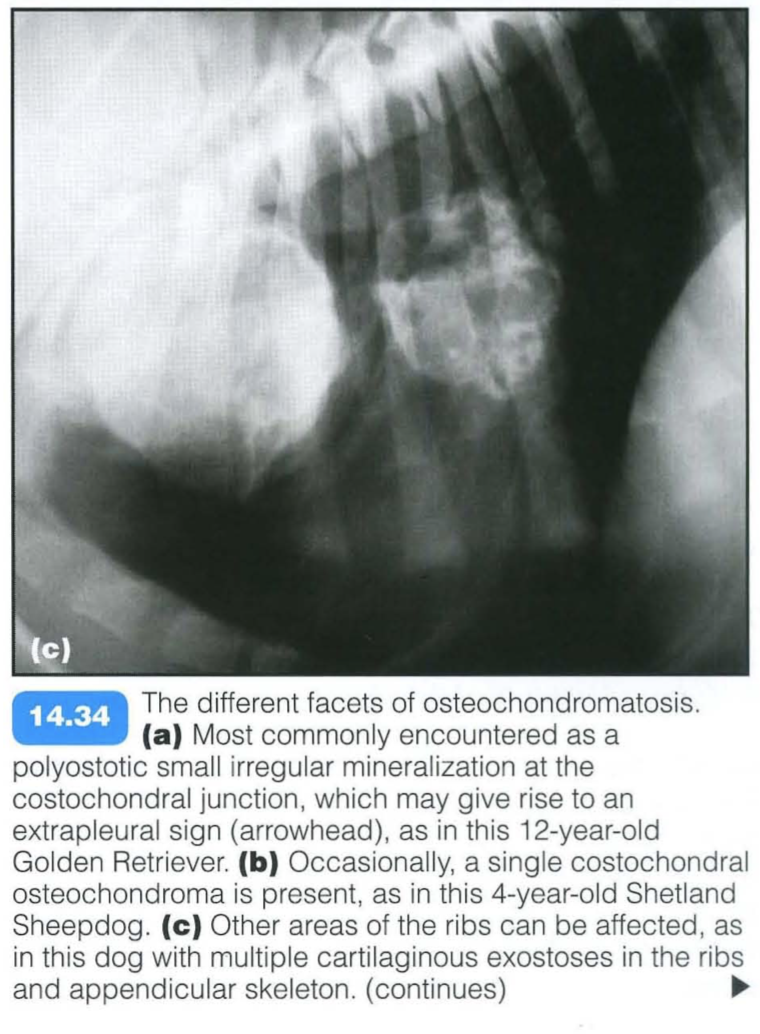

This is a skeletal dysplasia (a form of hamartoma) associated with expansile bony lesions, which usually arises from the osteochondral junction of bones. The lesion usually stops growing at the time of skeletal maturity.

In rare cases malignant transformation may occur. Commonly affected areas are the costochondral rib junctions; less frequently, the metaphyses of the long bones and vertebrae may be involved. Small rib lesions are common in dogs, but rare in cats. The condition can affect multiple sites simultaneously (multiple cartilaginous exostoses).

Clinical signs are usually related to lameness or paresis/paralysis in the case of spinal cord compression.

Other imaging techniques: CT or magnetic resonance imaging (MRI) may be used to assess spinal cord compression of vertebral osteochondroma.